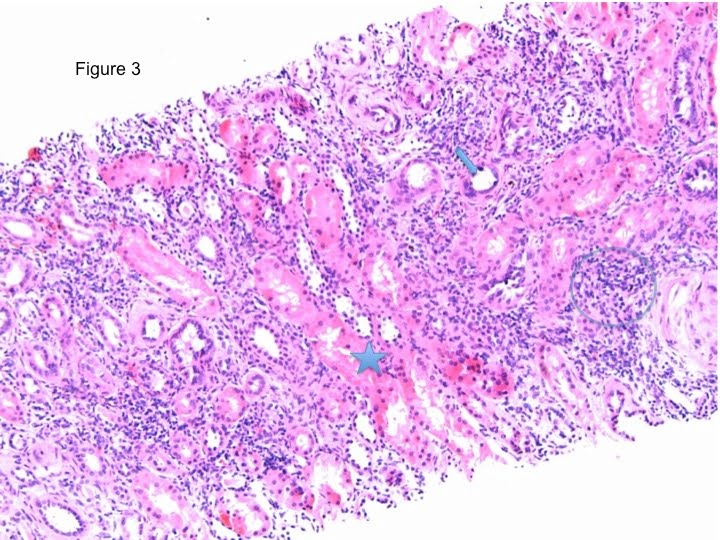

*Normally, the tubules should be packed and back-to-back, if infiltrates exist (Figure 3, blue small cells in the circle), we should be looking at the severity of the tubulitis in the most affected tubule. As you all know the more actively functional proximal tubule has a large strong eosinophilic cytoplasm (Figure 3, star) that differentiate it from the less active small cytoplasm of the distal tubules (Figure 3, arrow).

To differentiate between the tubular infiltrates and the tubular epithelium itself, compare those cells to the interstitial infiltrates, they should look similar. In addition the leukocytes in the tubules appears darker, sometimes with a hallow surrounding.